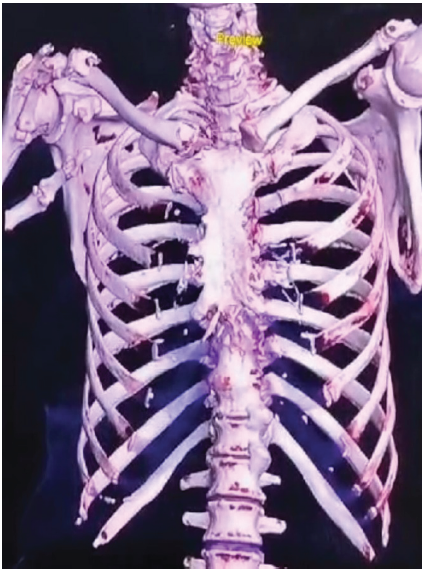

To assess any joint involvement, a computed tomography (CT) scan was done, which showed a comminuted, mildly displaced intraarticular fracture in the medial 1/3rd of the right clavicle and displaced oblique fractures in the lateral 1/3rd of the right clavicle with an intact acromioclavicular joint and sternoclavicular joint [Fig. 3].

Figure 3: Computed tomography scan, three-dimensional reconstruction of a bipolar clavicle fracture.